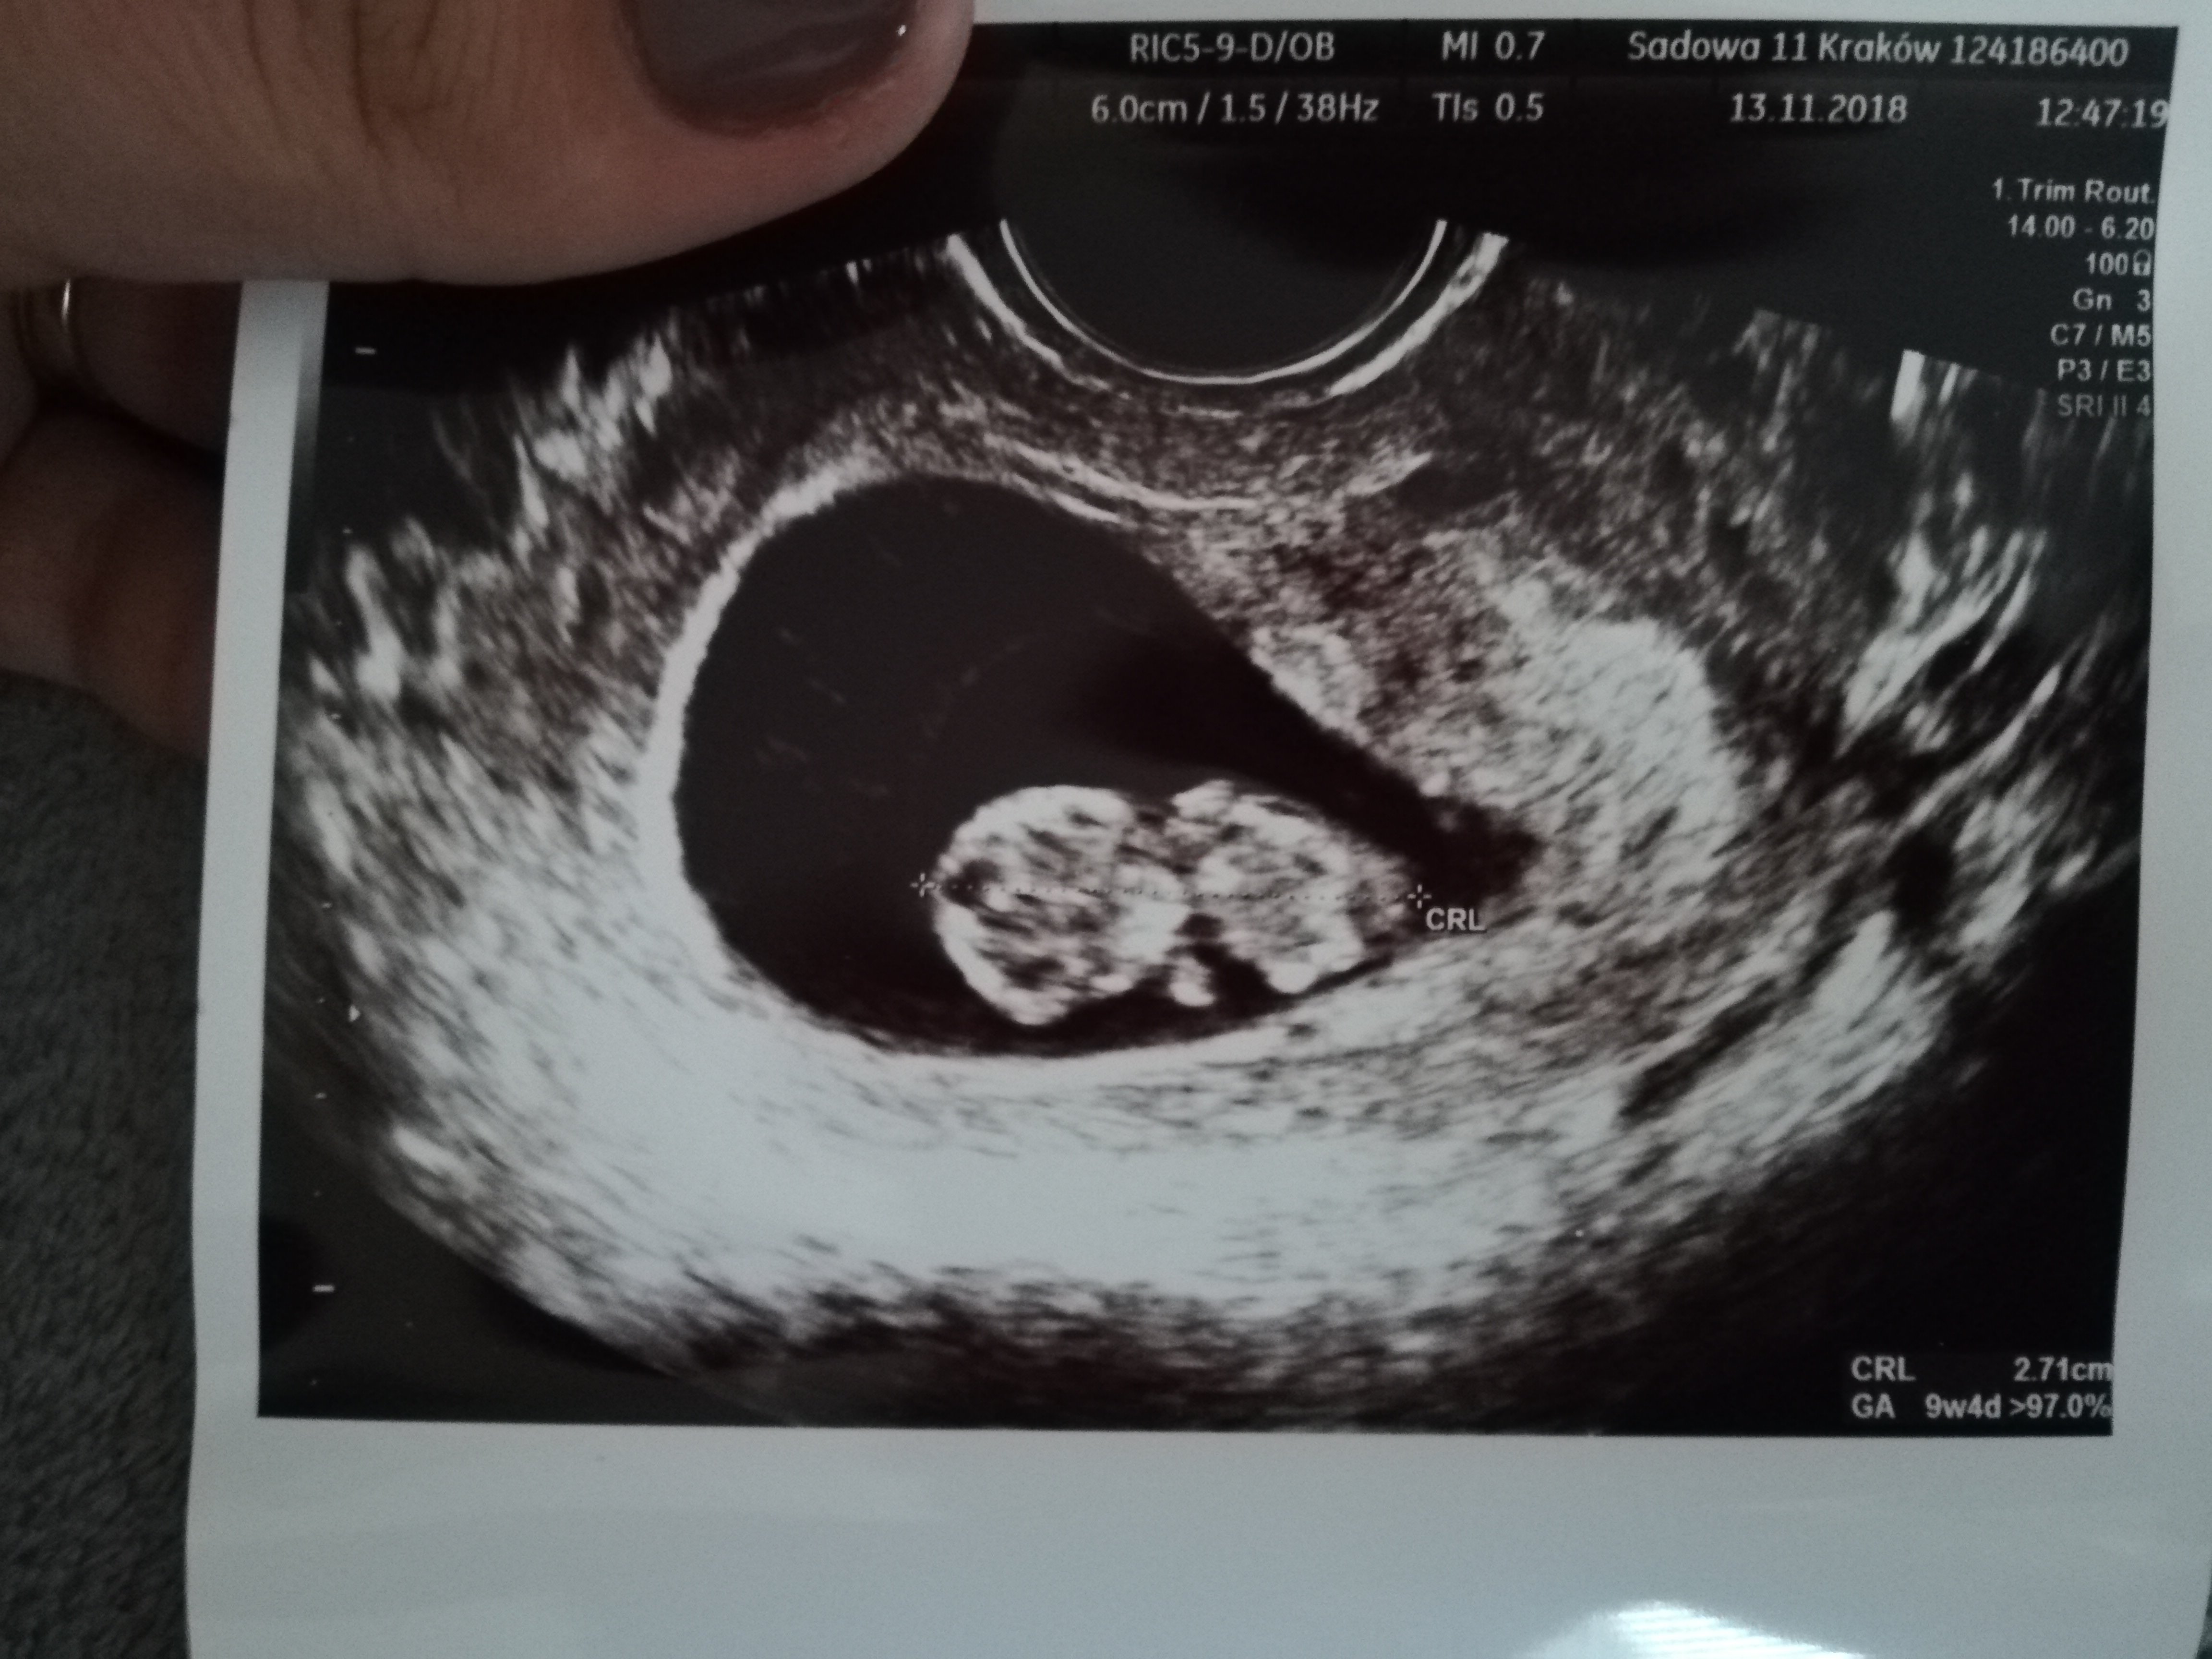

Byłam na wizycie i wszystko super. Serduszko bije, dzieciaczek ma 2,71 cm :) Dostałam wykaz badań, które muszę zrobić i aż się za głowę złapałam.

IMG_20181113_144935.jpg

• IMG_20181113_144935.jpg

180,3 KB · Wyświetleń: 376